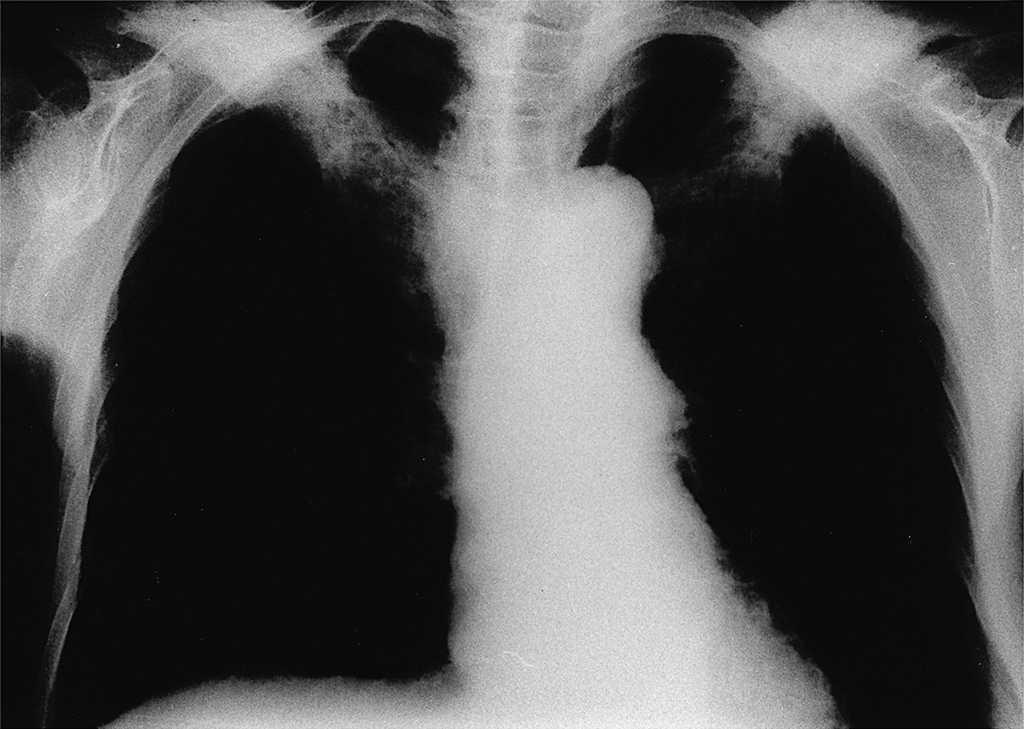

La gammagrafía ósea con 99-Tc (fig. 2) evidenció una hipercaptación del radionúclido en ambas clavículas, sin que se observaran otros cúmulos patológicos.

Figura 2. Gammagrafía ósea con 99-Tc: aumento patológico de captación del radioisótopo en ambas clavículas.